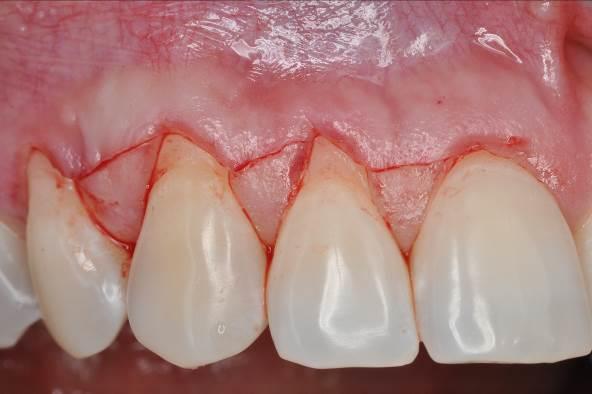

02/06 - Oblique incisions according to the modified coronally advanced flap technique (Zucchelli & De Sanctis J Periodontol. 2000).Multiple gingival recessions treated with the modified coronally advanced flap in conjunction with mucoderm® and Straumann® Emdogain® - Dr. D. B. Hangyási

05/06 - Complete coverage of the mucoderm® matrix and tension-free flap closure.Multiple gingival recessions treated with the modified coronally advanced flap in conjunction with mucoderm® and Straumann® Emdogain® - Dr. D. B. Hangyási